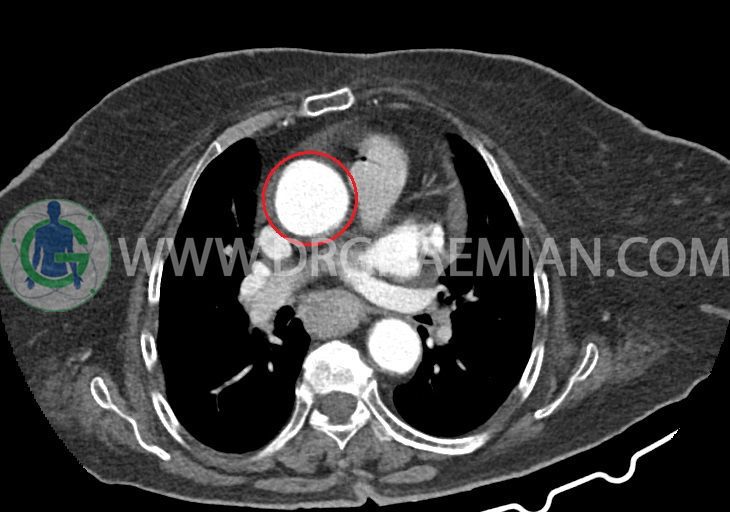

–کاردیومگالی همراه با pericardial effusion خفیف

–آئورت صعودی دیلاته به قطر 38mm

–یک ندول به ابعاد 19x18mm با حدود اسپیلوکه در سگمان لترال RML و دو ندول کوچکتر در مجاورت فوقانی آن به اقطار 6mm و 5mm ( مطرح کننده کارسینوم برونکوژنیک یا متاستاز )